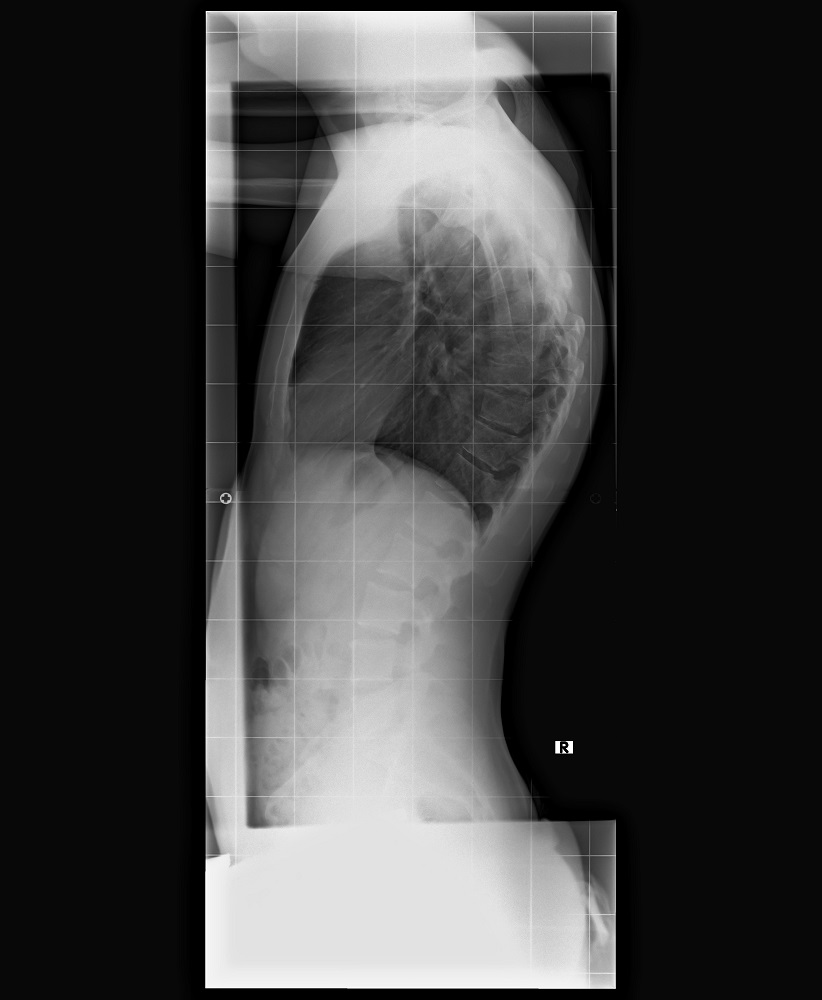

Um es kurz zu machen. Er sagt ich habe Scheuermann Kyphose. (Keilwirbel) Was für mich jedoch der Hammer war, es sind laut seiner Aussage über 80°

Laut seiner Aussage sieht er vielleicht eine mögliche Verbesserung mit Korsett Therapie auf 60°. Aber da kann er halt auch nichts versprechen. Bei manchen funktioniert es und bei anderen eben nicht. Mit Operation würde ein erheblich besseres Ergebnis entstehen.

Im Anhang findet ihr noch mein Bild von gestern.